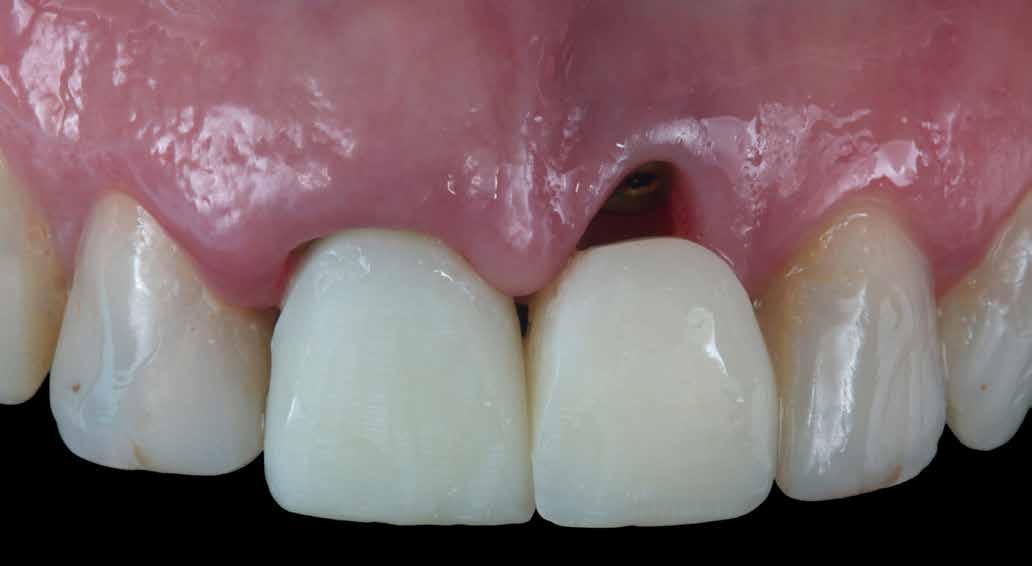

A front régióban alkalmazott minimál invazív multidiszciplináris megközelítés eredményeként jelentős mértékben tudtuk javítani a páciens esztétikai megjelenését. A beavatkozások során japán washi papír felhasználásával történő belső fogfehérítést, valamint háromdimenziós nyomtatással készült sebészeti sablon által vezetett ínyplasztikát végeztünk, majd az esztétikai zónában lévő fogakat – köztük egy elszíneződött nagymetsző fogat – ultravékony földpátkerámia héjakkal láttuk el.

A páciens elsősorban a mosolyának megjelenésén szeretett volna javítani. Egy előzetes állapotfelmérést követően az elszíneződött fog belső fehérítését, ínyplasztikát, valamint a felső front- és első kisőrlőfogak esztétikai célú helyreállítását javasoltuk. A belső fogfehérítés során nátrium-perborát és 30%-os hidrogén-peroxid keverékével átitatott washi papírt alkalmaztunk. Az anyag pulpakamrába történő helyezését követően az üreget üvegionomer cementtel zártuk. A fogfehérítés befejezését követően 3D nyomtatott sebészi sablont készítettünk, majd a felső front régióban megfigyelhető lágyrészek lefutását ezen sablon segítségével korrigáltuk. A sebészi beavatkozást követően 6 hónappal ultravékony földpátkerámia héjakat készítettünk.

A páciens elégedett volt a végleges restaurátumok színével, formájával és méretével. A kezelés végeredménye kielégítette az esztétikai elvárásait (9. ábra). A frissen átadott restaurátumok épségének megőrzése érdekében a páciens számára éjszakai fogvédősínt készítettünk. A páciensünk a négyéves kontrollvizsgálat során is nagyon elégedett volt a kezelés eredményével. A korábban meglévő fekete háromszögek eltűnésének különösképpen örült (9. és 10. ábrák)

9. ábra. A beavatkozás után, valamint a 4 évvel később látható állapot. (A): Egy héttel a ragasztás után készült felvétel. (B): A négyéves kontroll alkalmával készült felvétel.

Jelen esettanulmányban három meglévő technika kombinálását és továbbfejlesztését mutattuk be: washi papír használatával történő belső fogfehérítést, nyomtatott sebészi sablon által vezetett ínyplasztikát, és a fogakra ultravékony földpátkerámia héjakkal történő ellátását. E bonyolult eset kezelése során – minimálinvazív megközelítés mellett – kiemelkedő esztétikai eredményt sikerült elérni.

Az alapos tervezést követően végzett restauratív beavatkozások során sikeresen kombináltuk a washi papírral végzett belső fogfehérítést, a 3D nyomtatott sebészeti sablonnal és elektrokauterrel végzett ínyplasztikát, továbbá az ultravékony földpátkerámia héjakkal történő ellátást. A kezelési terv követésével el lehetett érni a kívánt esztétikai eredményeket, amelyek már 4 éve stabilnak bizonyultak.